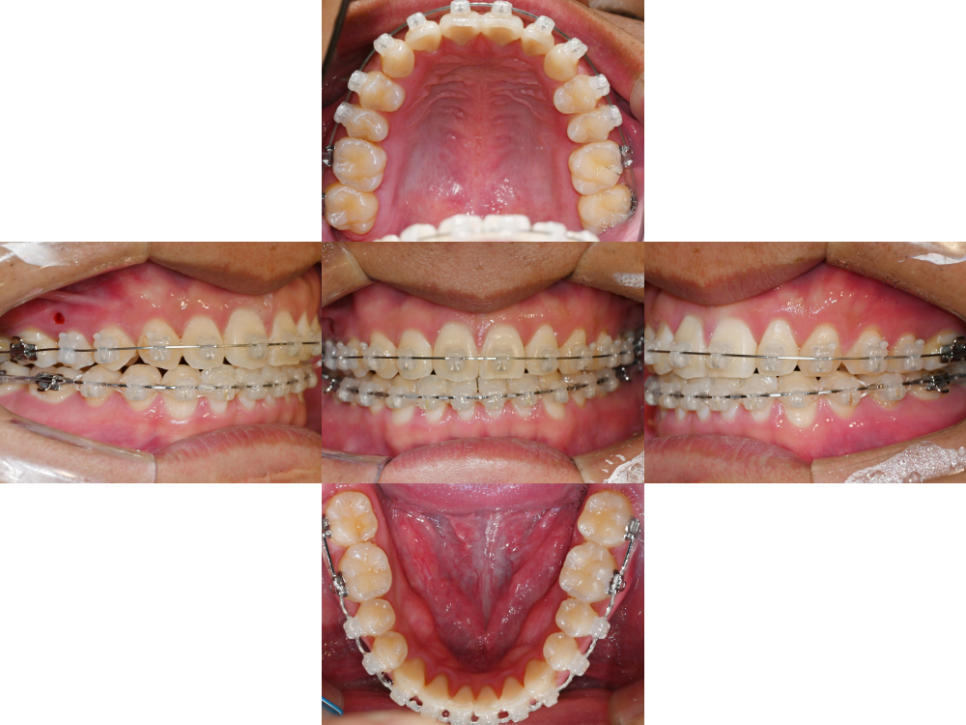

23.12.14

이 케이스의 경우

검사와 시뮬레이션을 통해

비발치 교정을 진행했습니다.

클리피씨 브라켓를 치면에 부착하고

오른쪽 윗니 주위에 미니 스크류 를 식립했는데요.

24.04.05

클리피씨 브라켓은

자연치의 이동 시 생기는 마찰력을 줄일 수 있어

통증의 정도가 경감될 수 있습니다.

더불어, 메탈에 비해

더 심미적이며 음식 끼임 정도가 적은데요.

24.08.28

이 덕분에 구강 위생 관리가

용이해진다는 특징이 있습니다.

동시에 정확한 치아 이동을 위해

오른쪽 위 쪽에 식립한

미니 스크류는 고정원의 역할을 담당하여

정확한 자연치 이동을 하는데

큰 도움을 줄입니다.

이러한 과정을 걸쳐

14개월의 치료 기간의

진료가 종결되었습니다.